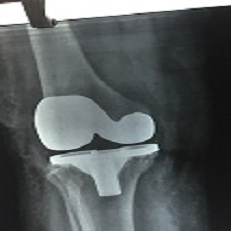

Tkr 69 Year Old

Tkr 73 Year Old